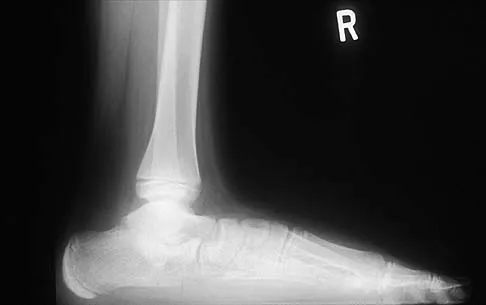

Question 53 High Yield

A 75-year-old woman began a walking program 2 months after undergoing right total knee arthroplasty. She had to stop the program after 4 weeks because of hindfoot pain and ankle swelling. Radiographs are shown in Figures 42a and 42b. What is the most likely diagnosis?

Detailed Explanation

It is often tempting to assign a diagnosis of plantar fasciitis in patients with hindfoot pain. In this patient, the radiographs confirm a diagnosis of a calcaneal insufficiency fracture. The dense condensation of bone on the lateral view confirms the diagnosis. There is no radiographic evidence of a heel spur, osteochondral lesions, or chondrocalinosis. Resnick D: Diagnosis of Bone and Joint Disorders, ed 3. Philadelphia, PA, WB Saunders, 1995, p 2591. Kearon C: Natural history of venous thromboembolism. Semin Vasc Med 2001;1:27-37.